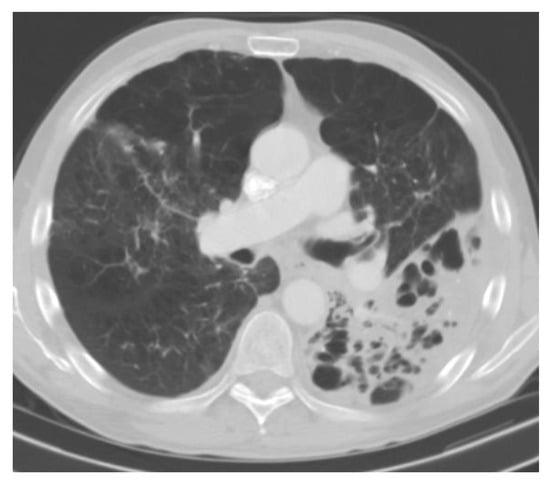

Symptoms are usually non-specific and may include fever, fatigue, and weight loss. Pulmonary symptoms may not be predominant and can include a dry cough and shortness of breath. Pulmonary imaging can show diffuse miliary-type reticulonodular infiltrates (Figure 8). Patients may present with hepatosplenomegaly, extrapulmonary lymphadenopathy, CNS lesions, and skin lesions. Gastrointestinal involvement is common and may mimic a cytomegalovirus infection. It can present with diarrhea, mucosal thickening, and ulcerations. Laboratory analysis may show cytopenia, hepatic enzyme elevation, and high lactate dehydrogenase.

Figure 8.

Progressive disseminated histoplasmosis. CT chest showing diffuse reticulonodular infiltrates with large mediastinal lymphadenopathies.